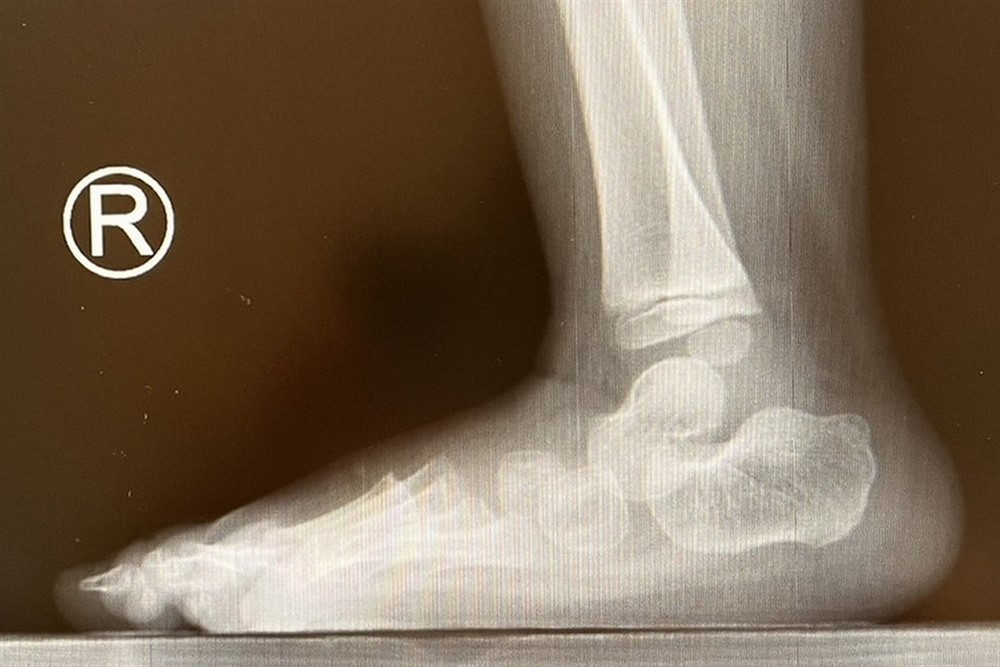

軒軒的腳自出生就無力,足弓塌陷,腳趾呈現爪狀趾,必須製作適合的鞋墊來改善。圖/台北慈濟醫院

邱佳儀醫師說,軒軒從出生開始腳的肌肉就沒有力氣,會因為肌力不平衡而導致關節變形,再加上感覺功能的缺損,皮膚容易磨損、長繭,因此會讓他穿上特殊鞋墊,防止足部肌肉關節的變形。

邱醫師一邊評估,一邊請軒軒站起來走一小段路,審視他的走路步態。接著,邱醫師告訴爸爸:「因為病灶的部位影響到足部,會有足弓塌陷及腳趾像爪子般彎曲的現象,我們等等會重新替軒軒製作新的鞋墊,才不會影響腳的變形與行走的步態。」